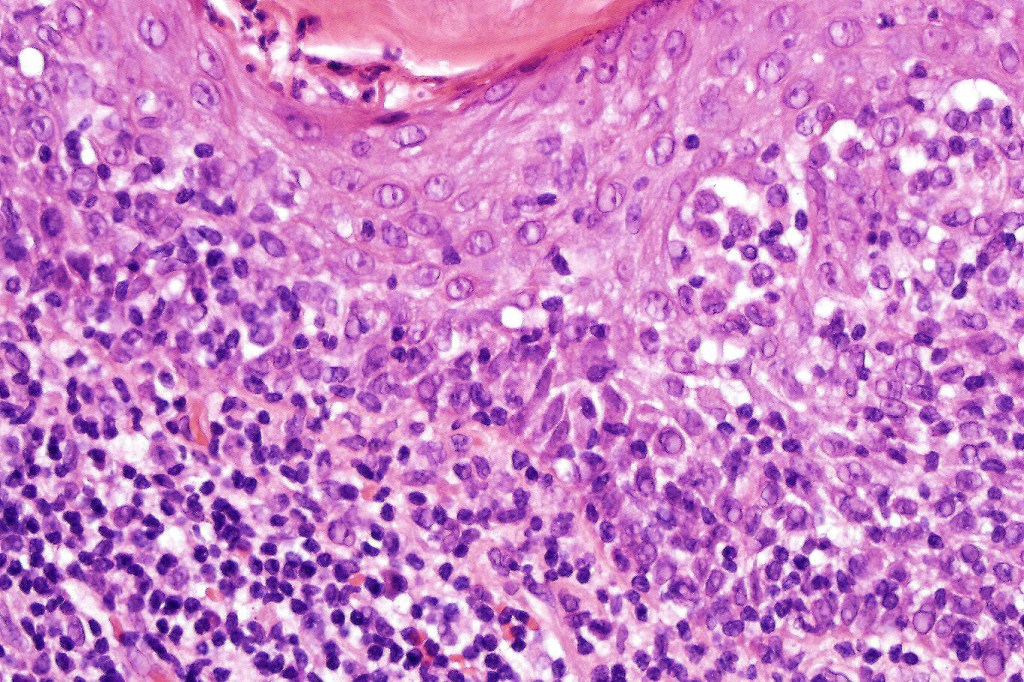

Histological features

•Follicular infiltration by atypical lymphocytes & Sézary cells

•+/- mucinosis

•+/- basaloid follicular hyperplasia

•Granulomatous inflammation secondary to follicular destruction